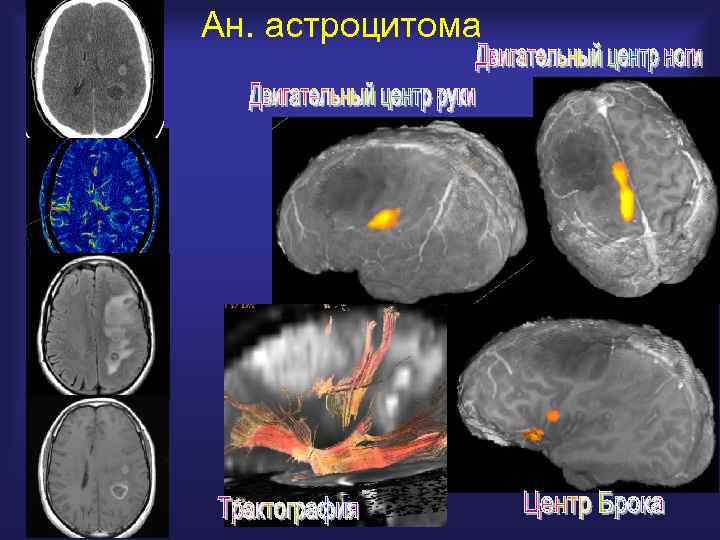

Ан. астроцитома

Функциональная МРТ ф. МРТ выявляет зоны нейрональной активации в коре мозга, помогая в планировании хирургического лечения, радиотерапии, в изучении нейрокогнитивных нарушений и их восстановление после операции и ЧМТ

ф. МРТ - позволяет получить комбинированное изображение, совмещающее анатомию мозга, поверхностные вены и карты активации (движение, речь, звук и др. ) - планировать хирургический подход к опухоли - планирование радиохирургии

Анизотропия диффузии и трактография ESNR 2005 ДВИ позволяет проводить картирование нервных трактов и открывает новые возможности в изучении механизмов работы мозга